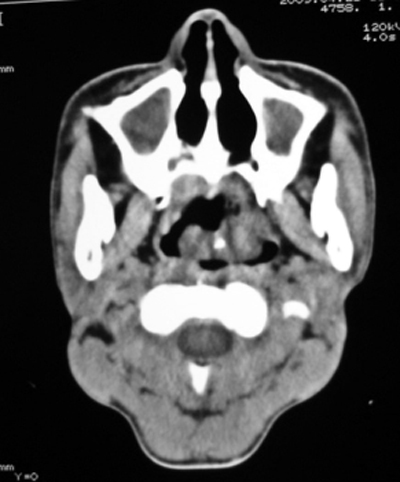

以下是引用随光逐影在2009-4-23 19:35:00的发言:[br]1)鼻咽、口咽、左侧鼻腔及右侧鼻后孔处新生物,考虑息肉可能性大。2)双侧上颌窦及双侧筛窦炎症,不排除双侧上颌窦内息肉可能。

以下是引用syfszcw在2009-4-23 13:21:00的发言:[br]双侧上颌窦 筛窦慢性炎症,鼻息肉 会厌ca[br][br][本贴已被 syfszcw 于 2009-4-23 13:36:46 修改过]

以下是引用bmw011在2009-4-23 13:23:00的发言:[br]考虑鼻息肉,上颌窦、筛窦炎